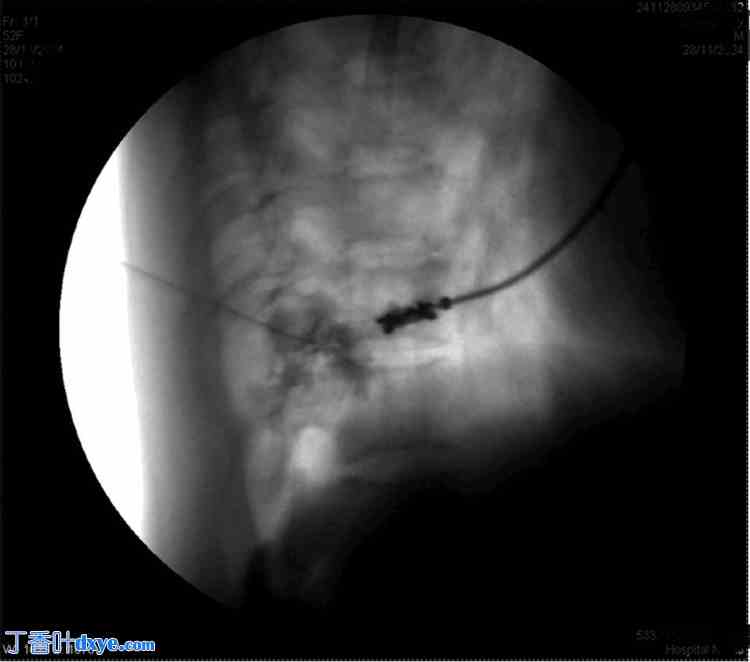

患者取俯卧位。涂抹并铺巾后,在C臂辅助下将T8横突定位于右侧。在透视引导下插入Quincke针(22 G),到达T8横突。针尖沿横突向尾部推进,直至感觉无阻力。在透视下注射碘海醇300放射性造影剂确认针头位置,并拍摄前后位和侧位图像(图1-4)。

图1. 针头位于T12横突处。